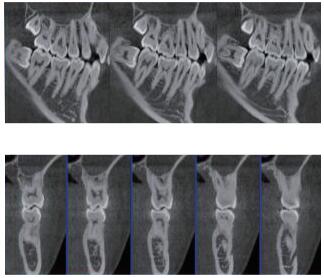

在口腔影像等細分領域,口腔CBCT的成像質量優于CT和普放。CBCT的X線利用率更高,且生成的圖像具備很高的各項同性空間分辨率。口腔CBCT能夠針對局部斷層曲面重建生成清晰無重疊的斷層影像以及3D影像,成像效果更好,有助于醫生的診斷,對于種植、綜合診斷、正畸等牙科診斷均有較大幫助??谇籆BCT技術優勢如下:

三維重建任意斷層

專有三維重建算法,可提供任意位置高清斷層影像。

可同時觀察軸向面、冠狀面和矢狀面圖像,方便臨床診斷。